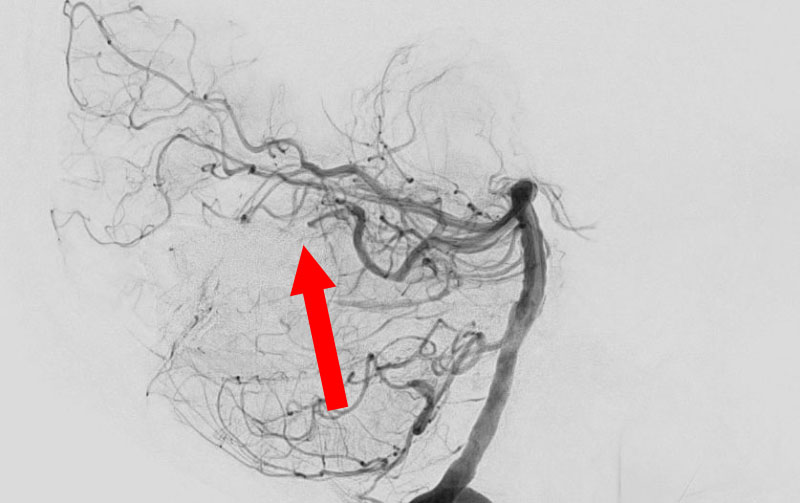

No.1594 手術後